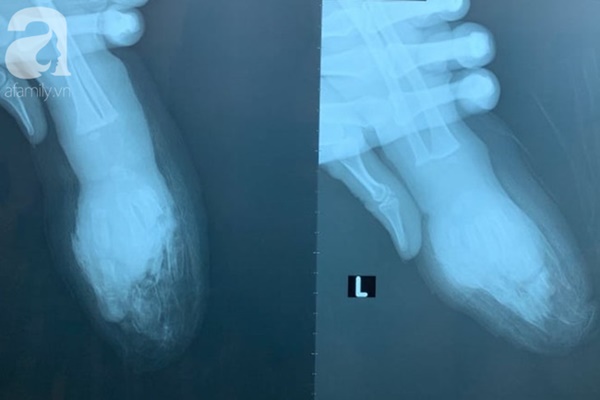

Ảnh chụp phim 2 bên bàn tay bé.

TS.BS Phan Đức Minh Mẫn, Trưởng khoa Chỉnh hình nhi, Bệnh viện Chấn thương chỉnh hình TP.HCM cho biết trước tình huống hết sức cấp bách trên, ekip điều trị đã nhanh chóng cắt lọc vết thương, xuyên 4 đinh giữ trục và nối vi phẫu 4 ngón tay bên trái cho bệnh nhi.

Quá trình phẫu thuật, các bác sĩ đã nối tận - tận 1 động mạch và ghép 2 động mạch ghép tĩnh mạch, nối 3 tĩnh mạch, nối 2 dây thần kinh, nối toàn bộ gân gấp.